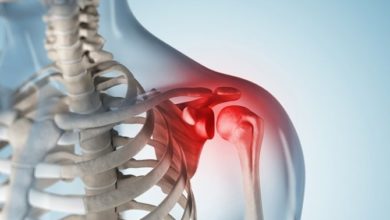

Rotator kılıf yırtığı

Rotator kılıf sorunlarına genellikle ağrı eşlik eder. Bu ağrı corocoacromial ark ve deltoid orta veya ön kısmında hissedilir. İstirahat sırasında…

İmpingement sendromu-sıkışma sendromu

Kolun omuzdan öne kaldırılması ve iç döndürülmesi esnasında omuz kemiğinin altındaki bölgede ağrı oluşması ile karakterizedir. Prof. Dr. Mustafa ÜRGÜDEN Ağrının…

Omuz eklemi kireçlenmesi

Pek çok hastalık(romatoid artrit, osteoartrit, posttravmatik artrit ve osteonekroz, vs) omuz ekleminde tahribata ve eklemde kireçlenmeye neden olabilir. Enfeksiyon ve…